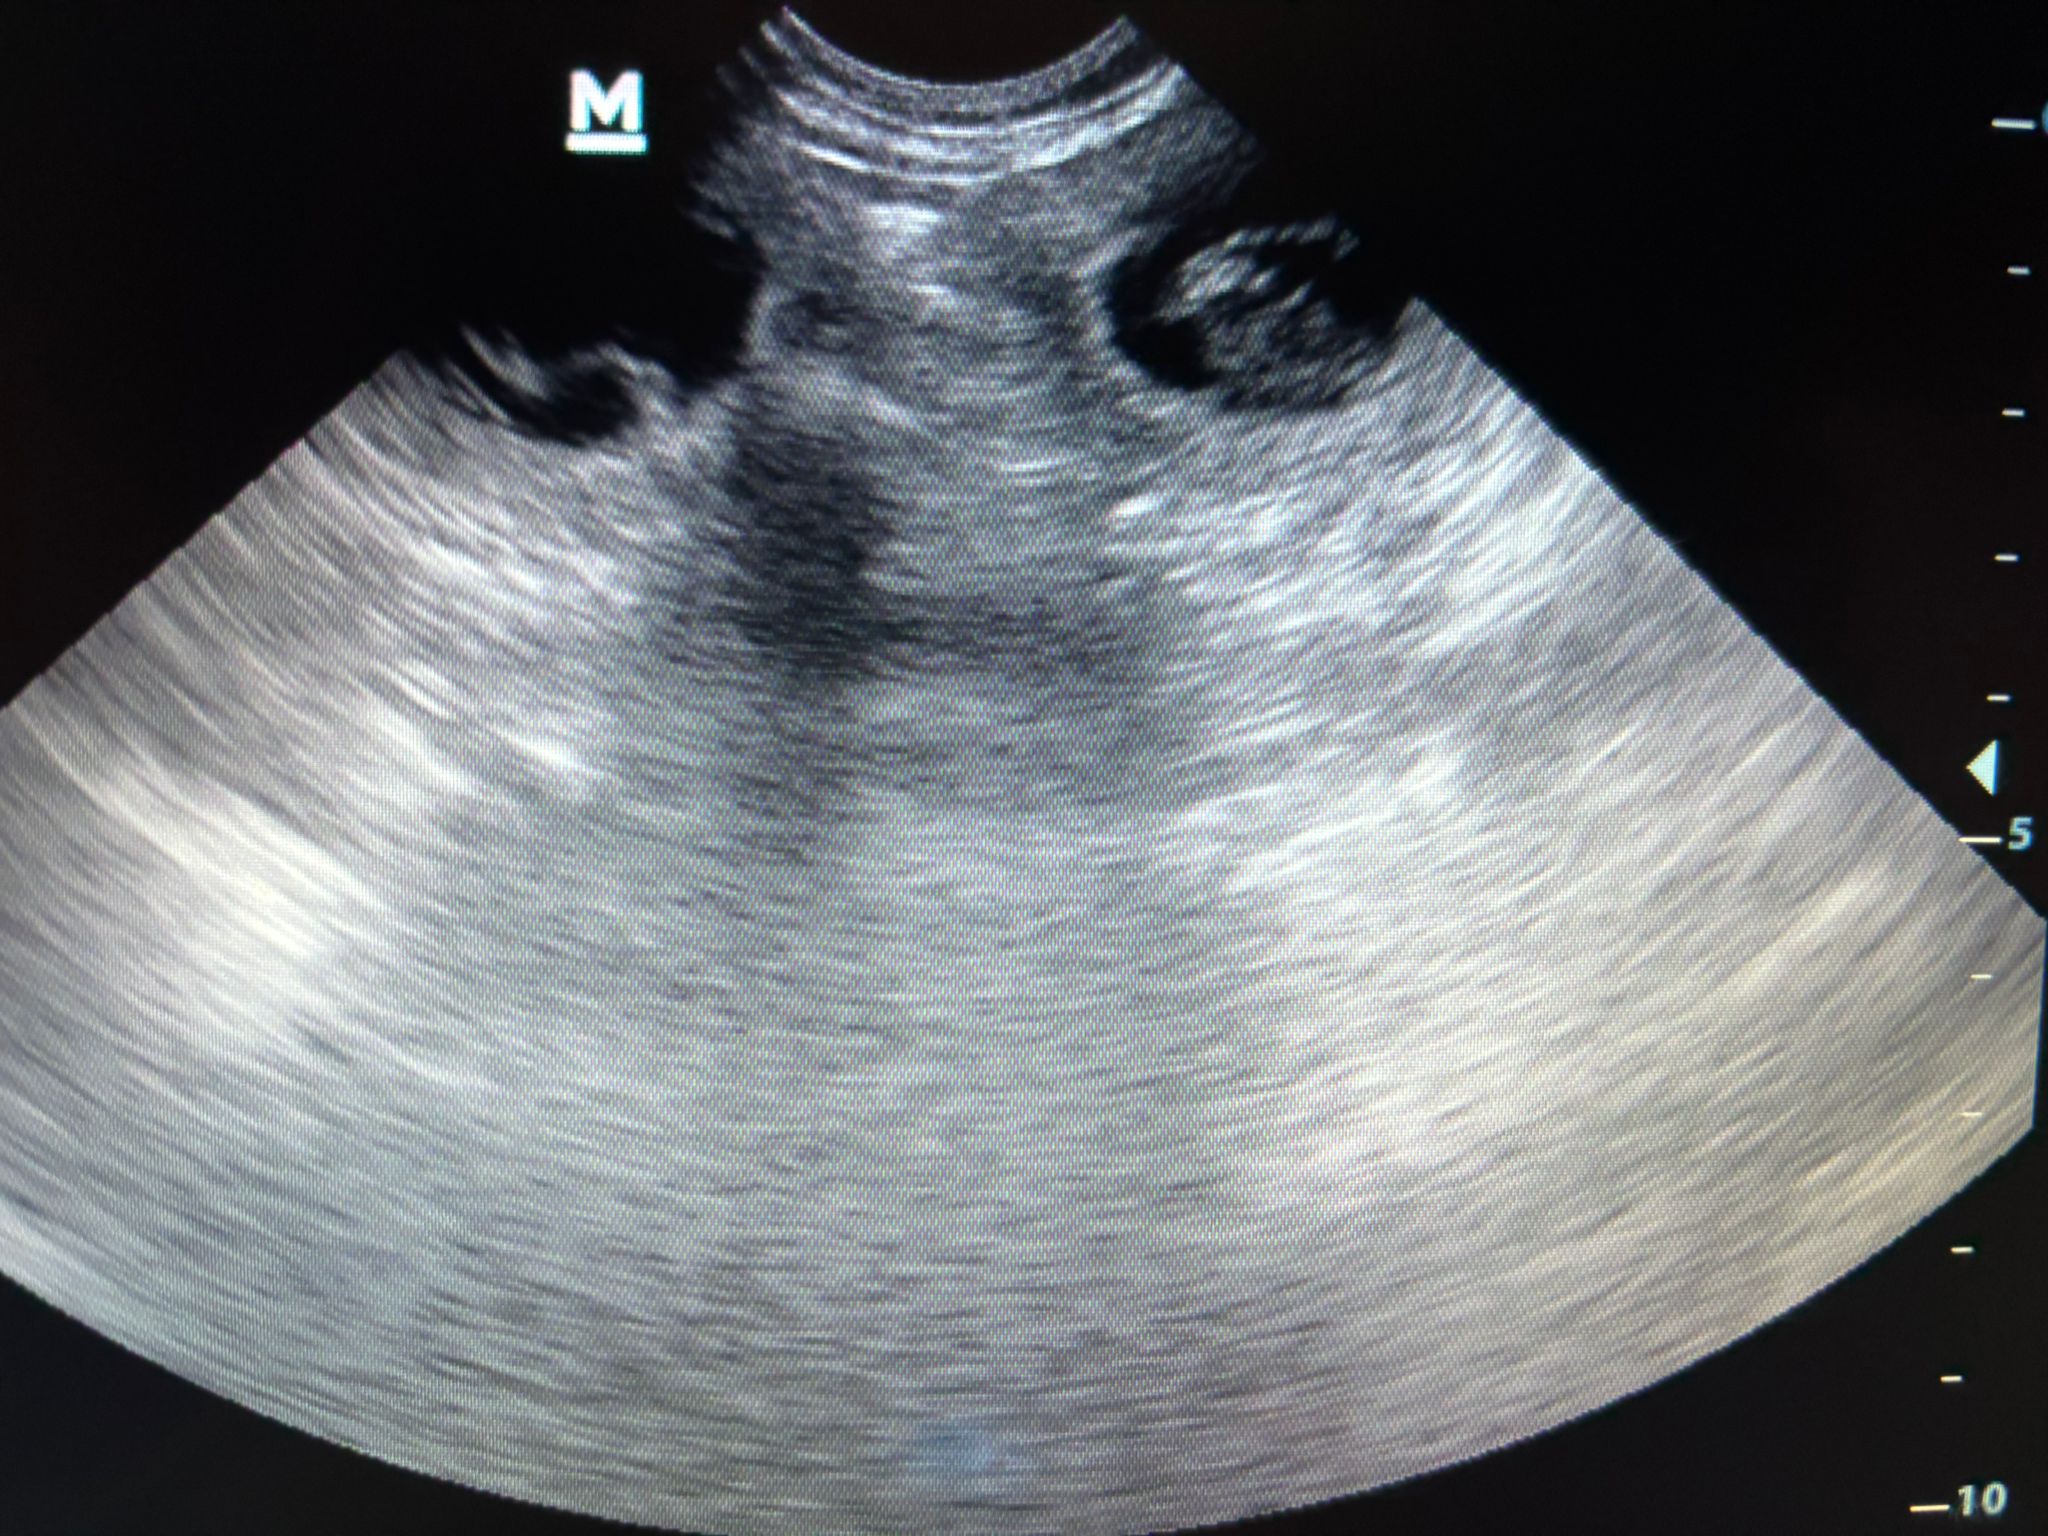

Beim Ultraschall bei unserer Tierärztin hat sich gestern Abend (19.2.2026) gezeigt, dass unsere Maite vom Nikolausberg nun trächtig ist und aus der Verpaarung mit unserem Duke Ellington kleine English Cocker Spaniel Welpen bekommen wird. Wir sind schon so gespannt auf den A-Wurf.

Am 26. März 2026 wäre der berechnete Wurftag aufgrund des 1. Deckakts. Der Ultraschall zeigt aber wohl, dass sie noch kleiner sind und ein späterer Deckakt wahrscheinlich dazu führte.

Deshalb ist es wahrscheinlicher, dass der Wurftag auch ein paar Tage später sein könnte. Eine fast genaue Anzahl der Welpen können wir erst beim Röntgen sehen, das ca. 1 Woche vor dem Wurftag erfolgt. Dann lassen wir uns überraschen, wieviel Rüden und Hündinnen es sind, und welche Farben sie haben, wenn es soweit ist...